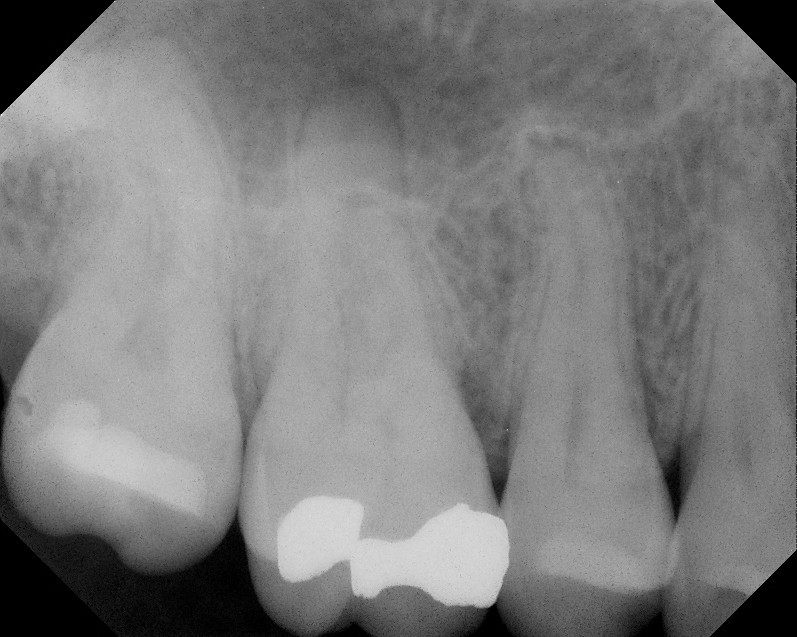

This patient came to our office in early 2010.  She was reporting throbbing pain to temperature that had been bothering her for a couple of weeks.  She also reporting biting pain.  Diagnostics found #3 was normal to cold test, normal to probing, mild pain to percussion, pain to biting pressure.  DX; #3 reversible pulpitis with symptomatic apical periodontitis and cracked tooth syndrome.  We decided to treat endodontically before a crown would be placed.

Upon accessing the pulp, we found a stained crack on the mesial and smaller crack on the distal.  Pt was informed that these cracks would not be completely removed, and would affect the long term prognosis for the tooth.  The patient, understanding that the prognosis is guarded, elected to preserve the tooth as long as possible by completing the RCT and placing a crown.